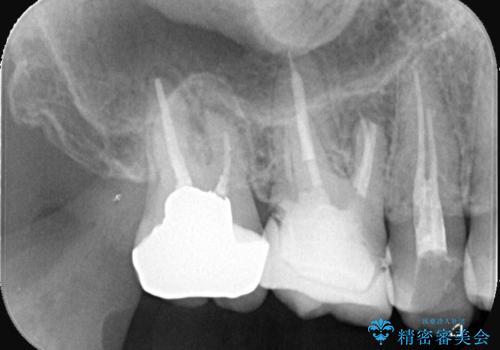

- 「銀歯を白くしたい」が主訴の患者様です。

銀歯を除去後、オールセラミッククラウンで治療を行いました。

被せ物のやり変えのみ希望だったため、根管とコアはさわっていません。

銀歯と虫歯を除去後、オールセラミッククラウンで治療を行いました。